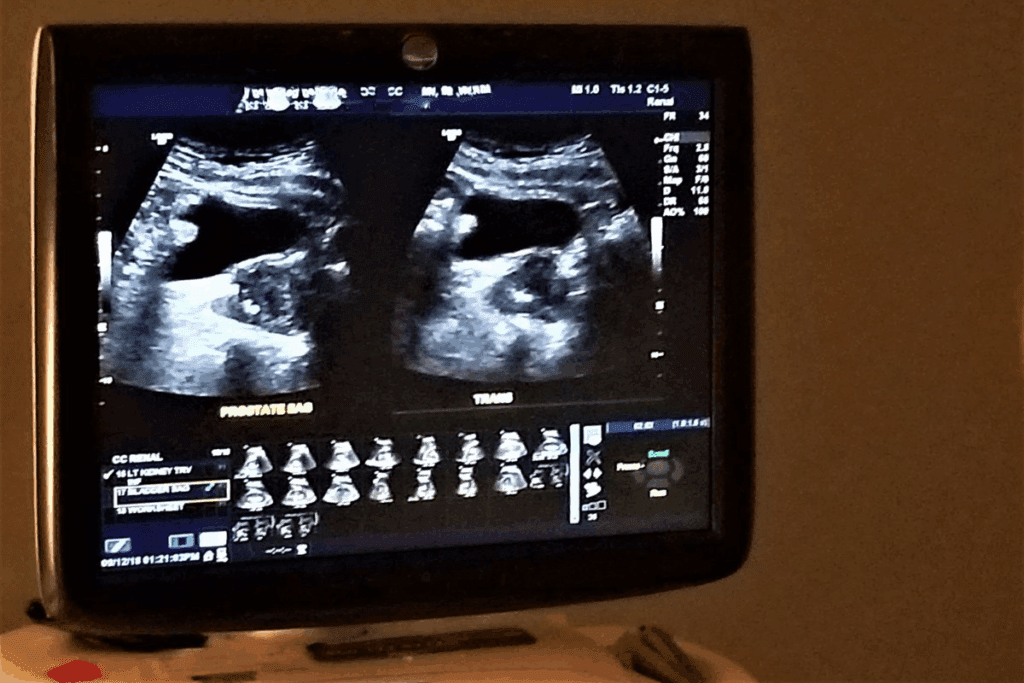

A pelvic ultrasound uses a device called a transducer. It sends sound waves that are too high for us to hear. These waves go through the skin and into the pelvis, making detailed images.

During a pelvic ultrasound examination, the transducer picks up echoes from organs. It turns these echoes into images on a screen. Doctors can then see the health of the pelvic organs.

Pelvic ultrasound works by using sound waves. These waves travel through tissues and bounce back when they hit something different. The transducer sends and receives these waves, showing a real-time image of the pelvis.

This lets doctors see the uterus, ovaries, and other parts of the pelvis. The images help find problems, check on pregnancies, and guide treatments.

Types of Pelvic Ultrasound Procedures

Transabdominal Ultrasound Overview

Transvaginal Ultrasound Explained

Transvaginal ultrasound uses a special transducer in the vagina. It gives clearer pictures of the reproductive organs. This is great for detailed checks.

When Both Methods Are Used Together

Doctors often use both transabdominal and transvaginal ultrasounds together. This way, they get a full view and detailed images. It’s a thorough way to check the pelvic area.